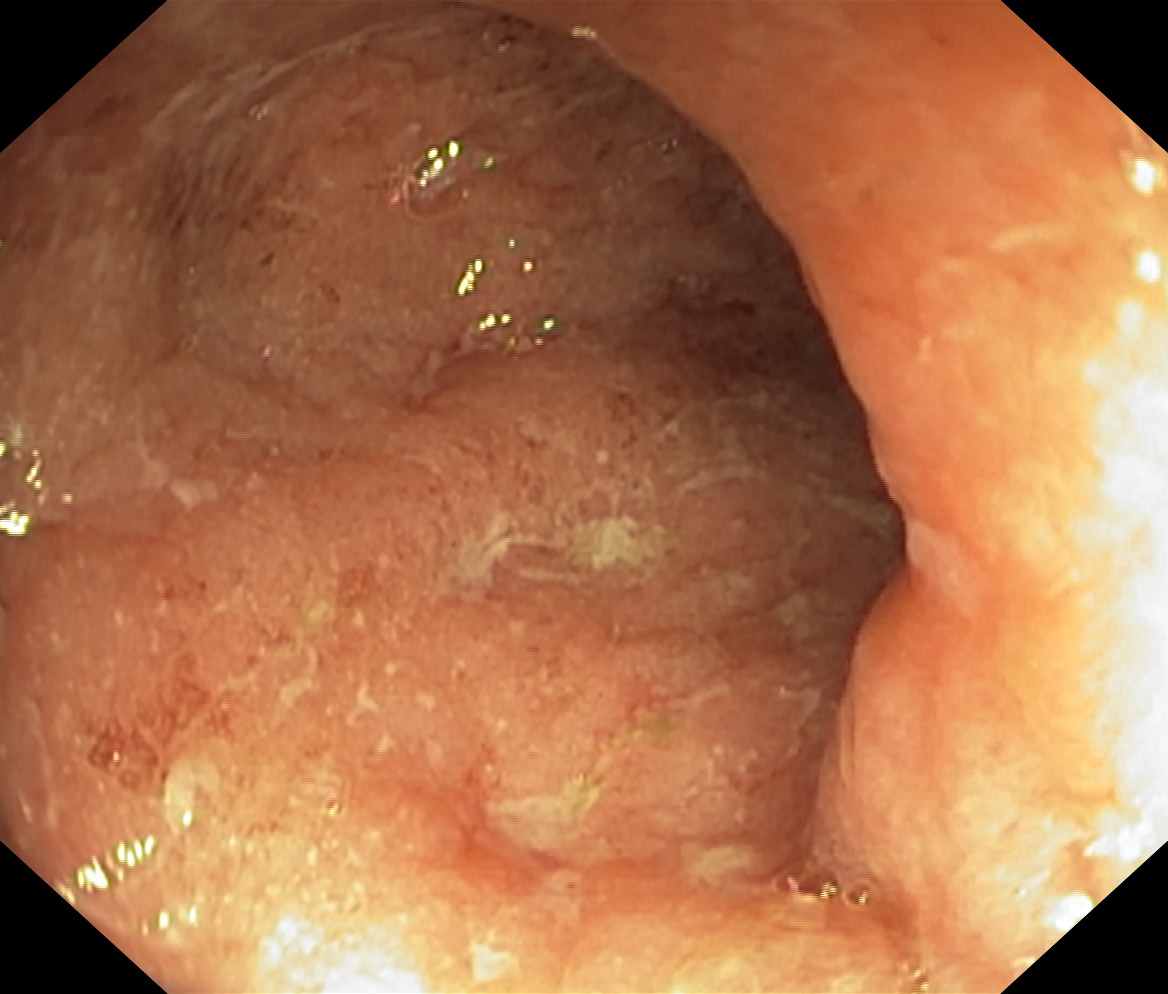

Obrazy endoskopowe

Nowotwory przewodu pokarmowego